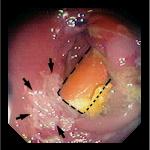

- 7-8. 72-летний пациент был доставлен с кровотечением из прямой кишки. За 48 часов до этого он вставил себе в прямую кишку резиновую трубку, которую не смог извлечь. При ректороманоскопии был обнаружен нижний край инородного тела, слизистая вокруг была воспалена и содержала язвы (обозначены стрелками на фото 8). Трубка была извлечена.